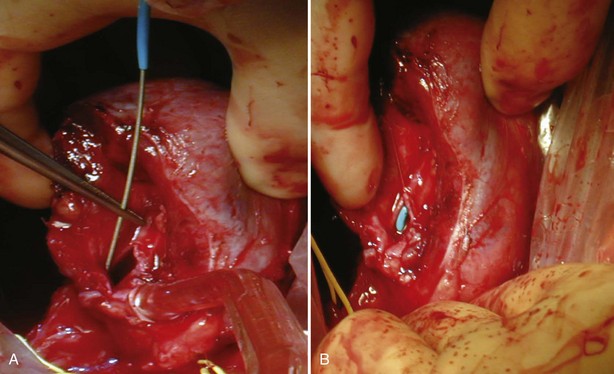

Figure 54–95 A and B, The renal artery and vein are secured and divided.

(Reproduced with permission from Novick AC, Streem SB, Pontes E, editors. Stewart’s operative urology. 2nd ed. Baltimore: Williams & Wilkins; 1989.)

For large renal tumors, especially those of the upper pole, the thoracoabdominal approach is preferable to an anterior approach (Fig. 54–92; see Fig. 54–93 on the Expert Consult website

). On the right side the liver is retracted cephalad. The hepatic flexure of the colon and the duodenum are reflected medially, exposing the IVC, the renal pedicle, and the anterior surface of the kidney (Figs. 54-94 to 54-96). The renal artery and vein are handled as described for the anterior approach. The ureter and right gonadal vein are ligated and divided. The kidney is mobilized outside the Gerota fascia down to the psoas fascia. The additional vascular attachments to the upper pole tumor and adrenal gland are exposed by medial retraction of the IVC along with caudal and lateral retraction of the kidney. They are ligated and divided. A curved-shaped clamp is passed along the superior portion of the adrenal gland to gain control of the phrenic vessels using a 0 silk suture ligature. The specimen is mobilized fully away from the liver and removed en bloc.

Figure 54–94 Exposure of large right upper pole tumor through a thoracoabdominal incision.